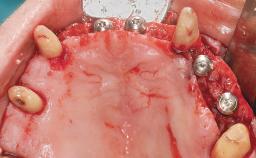

Immediate Loading of Six Implants in the Maxilla and Final Restoration with a Full-Arch CAD/CAM Zirconia FDP

A 63-year-old male patient was referred for a consultation and treatment of partial edentulism in the maxilla. The patient presented with residual anterior teeth and declined a partial removable prosthesis. He reported that the maxillary posterior teeth had been extracted due to mobility and periodontal disease two months before the consultation. The patient’s chief complaint was that his residual maxillary teeth were mobile and that he was unable to chew. The patient’s desire was a stable and comfortable fixed maxillary rehabilitation. The patient was a light smoker (fewer than 10 cigarettes/ day), and his medical history was without significant findings. He was not on any regular medication at the time of consultation. The extraoral examination revealed a normal physiognomy with a correct distribution of the facial thirds. The patient presented a low lip line, and the transition line between teeth and soft tissues was not exposed during a forced smile.

# of Implants 6

Type of Implants One-Piece

Defining Characteristics Fully edentulous upper jaw to be rehabilitated with four or more implants

Modality 6+ implants with immediate loading